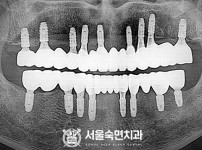

임플란트-전후사진2